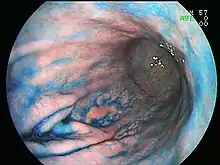

Endoscopic image of adenocarcinoma of duodenum seen in the post-bulbar duodenum..png.webp) Endoscopic image of gastric antral vascular ectasia seen as a radial pattern around the pylorus before (top) and after (bottom) treatment with argon plasma coagulation

Endoscopic image of gastric antral vascular ectasia seen as a radial pattern around the pylorus before (top) and after (bottom) treatment with argon plasma coagulation Endoscopic image of Barrett's esophagus, which is the area of red mucosa projecting like a tongue.